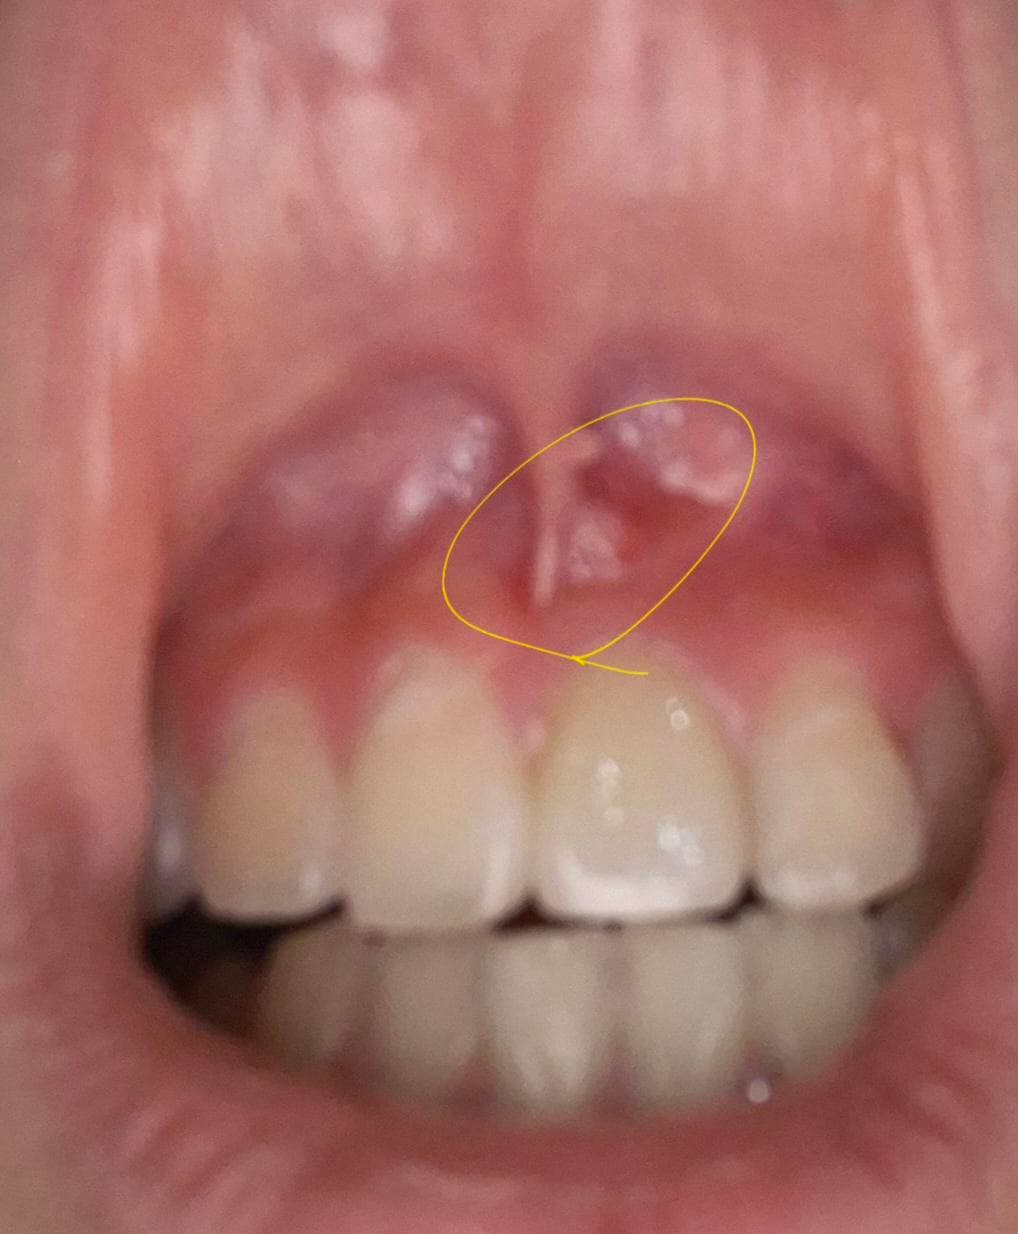

잇몸에 작은 이물감이 있어요 어떻게 해야 하나요?

일어나서 잇몸에 이물감이 들어서 봤더니 이래서요

뭔지 궁금합니다 큰일인가요? 피가 가거나 하진 않아요

사진으로 봤을 때는 근단치주염일 가능성이 높습니다. 치아 내부에 신경이 감염이 되면 뿌리 쪽의 염증을 형성하게 되는데 이런 염증이 외부로 드러나게 되면서 사진과 같이 고름이 찰 수 있습니다. 이런 경우 재신경치료나 치근단 말이 절제 설정이 필요할 수 있습니다.

잇몸이나 치아 속 신경의 염증 때문에 농양이 잡혔습니다 배농을 해주고 잇몸치료 내지는 신경치료를 해야 합니다